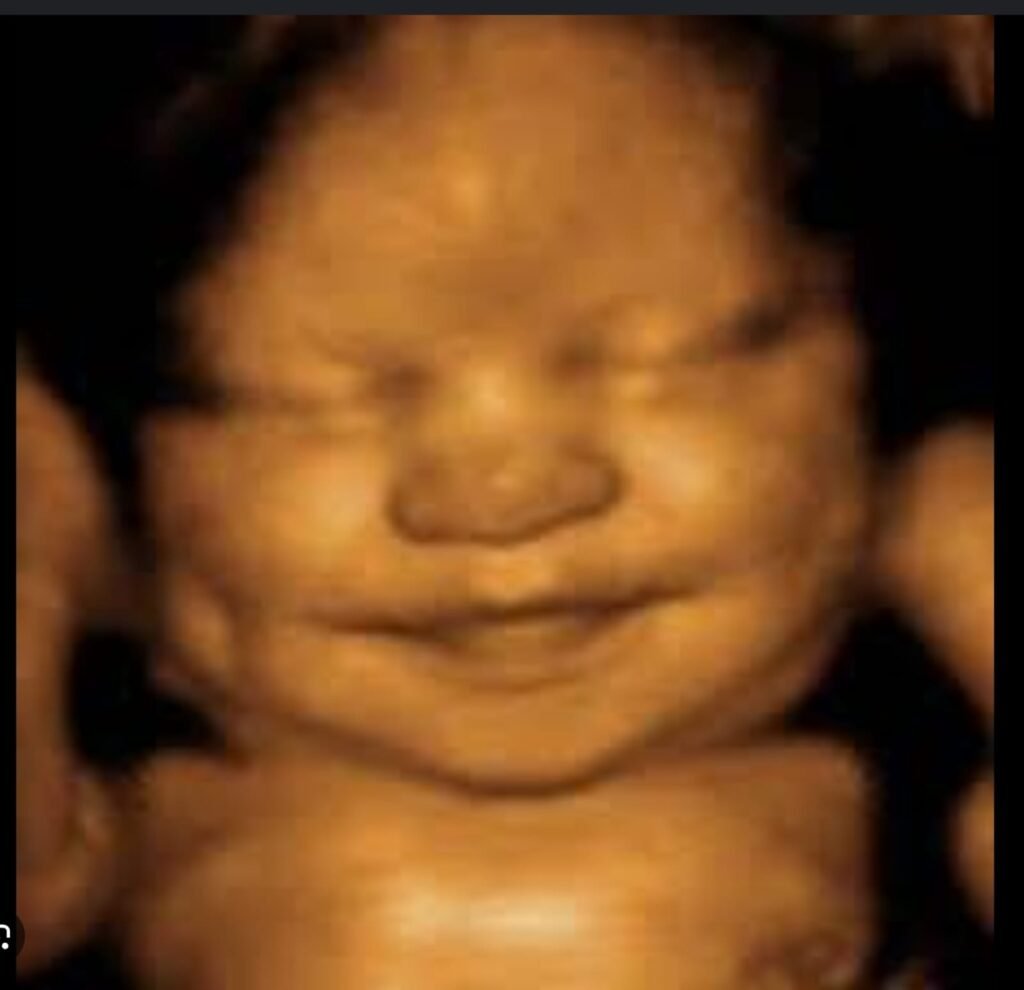

4D Bonding Ultrasound

Emotional connection meets medical imaging

See your baby’s movements, facial expressions, and personality in stunning detail.

Features:

3D/4D imaging clarity

Real-time fetal motion

Complimentary keepsake images

(Not a diagnostic scan — offered as a bonding experience when medically safe.)